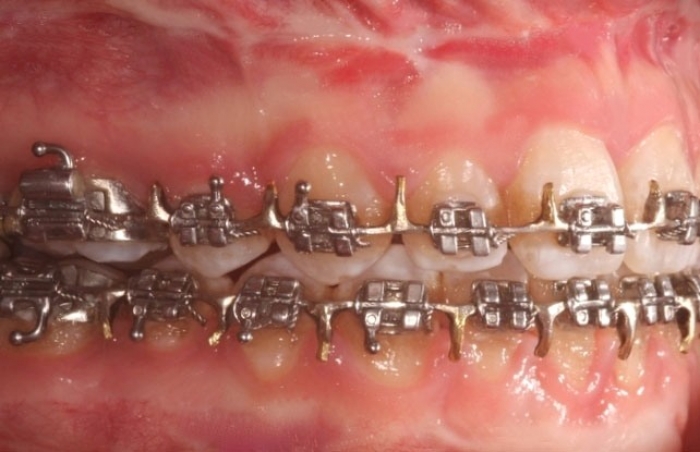

Mordida inicial